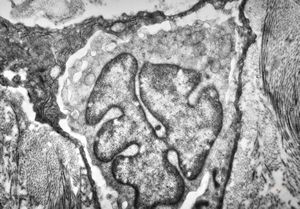

M, 48y. | multiplication of dermal perivascular basement membranes (unclassified myopathy)